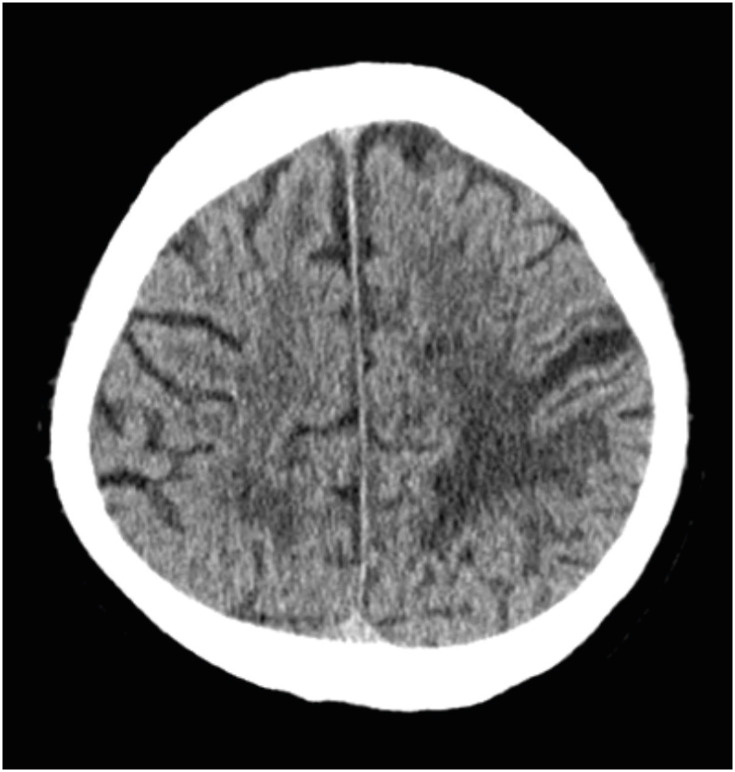

Intracerebral hemorrhage (ICH) is the second most common stroke subtype associated with high morbidity and mortality rates. Although various brain regions are susceptible to ICH, putaminal hemorrhage is the most common, whereas cortical ICH is less common. Here, we report the case of a 69-year-old man who developed a parietal cortical ICH. The patient developed hypoesthesia and paresthesia in the right upper lip and hand; however, the weakness was not severe. Twenty-five days after the ICH onset, the manual muscle test results were normal, but he had difficulty eating and shaving because of decreased hand dexterity. The rehabilitation focused on improving fine hand motor function and endurance. On the 94th day after ICH onset, paresthesia remained only in the fingertips, and the upper lip sensory change disappeared. Patients with sensory symptoms in the perioral area, hands, and brain lesions were previously referred to as having cheiro-oral syndrome (COS). With the advancement of neuroimaging, the use of this term has decreased, as cerebrovascular events can explain patient symptoms in correlation with neuroanatomy, etiology, and pathogenesis. We report a patient with cortical ICH, also known as COS, which is a stroke syndrome with a good prognosis.